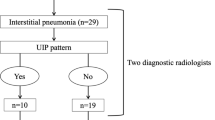

The present study included patients who were diagnosed with lung cancer and treated with PBT between January 2009 and 2015 at the Southern Tohoku Proton Therapy Center. Patients were retrospectively recruited from our database. The clinical stage of the patients’ lung cancer (Union for International Cancer Control, 8th edition) was determined using computed tomography (CT) and positron emission tomography (PET)-CT. Written informed consent was obtained from all of the patients. The inclusion criteria were as follows: patients aged ≥80 years when the patint received PBT; a solitary lung tumor; pathologically proven non-small cell lung cancer (NSCLC); a World Health Organization performance status of 0–2; no lymph node metastasis; and the absence of distant other organ metastasis or other sites of uncontrolled cancer. Any patients who received concurrent chemotherapy, and those with interstitial pneumonitis were excluded. The judgment as to the operability was made by a conference of lung surgeons. All operable patients who received PBT refused to receive lung surgery.

The initial study population included 78 patients aged ≥80 years who had received PBT for a lung tumor. Patients were excluded from the analysis for the following reasons: lymph node metastasis (n = 28); distant other organ metastasis (n = 3); interstitial pneumonitis (n = 4); and absence of NSCLC pathology (n = 8). Thus, the characteristics of 35 patients, including 25 (71%) with clinically inoperable NSCLC, were analyzed (Table 1). All patients completed treatments. The cohort comprised 26 men and 9 women, with a median age of 82 years (range: 80–87 years). The comorbidity index of 30 patients (86%) was ≥1. The median follow-up time was 34 months (range: 10–72 months). The median dose of PBT was 80.0 Gy (range: 60.0–80.0 Gy [RBE]).